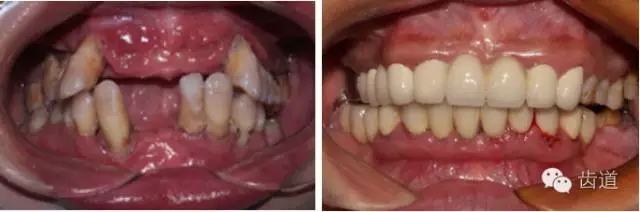

2、牙齦

(顏色、形狀、質(zhì)地、退縮、BOP、PD、附著齦)

6.webp.jpg

7.webp.jpg

8.webp.jpg

9.webp.jpg